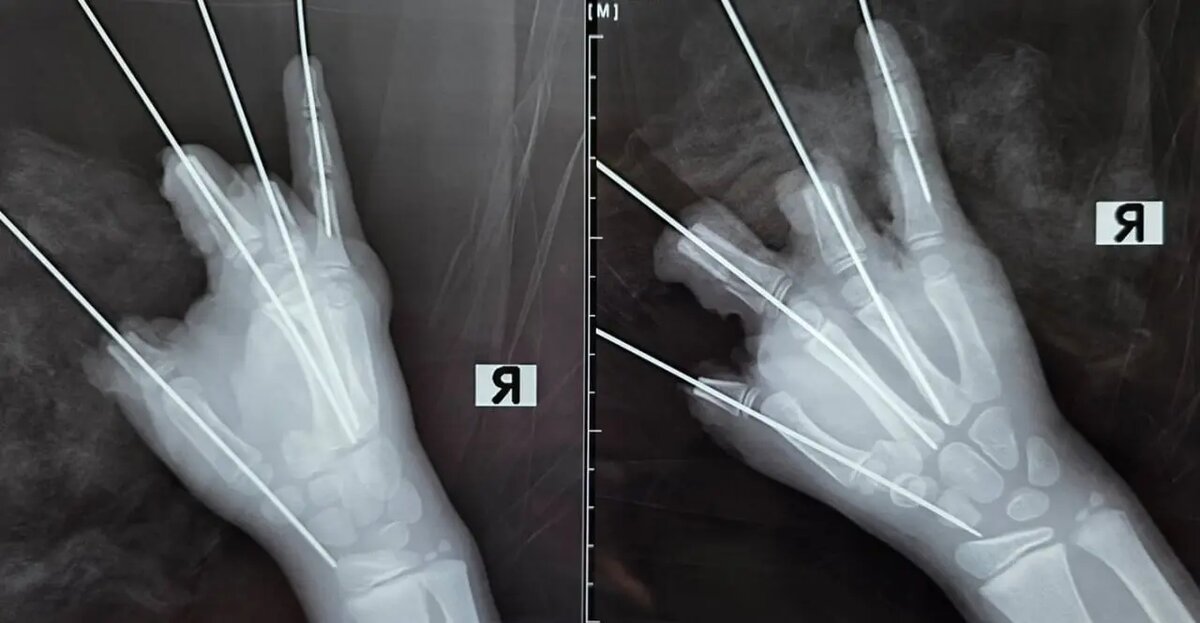

Фото: пресс-служба Педиатрического университета.

Инцидент произошел вечером 11 февраля во время прогулки. У него в правой руке взорвалась петарда. Это привело к потере четырех пальцев — большого, указательного, среднего и безымянного. Кроме того, пострадали мягкие ткани, и мальчик получил открытый перелом и вывих пястной кости.

Пострадавшего отправили в Педиатрический университет, где ему сразу начали операцию. Она длилась пять часов. За это время хирурги удалили разрушенные ткани, соединили костные фрагменты и сформировали культи пальцев. Сейчас ребенок в реанимации. Однако в ближайшие дни возможен некроз оставшихся тканей, сообщили в пресс-службе университета.